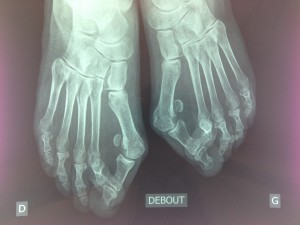

Le diagnostic repose essentiellement sur l’examen clinique du pied complété par un bilan radiographique et ou podoscopique.